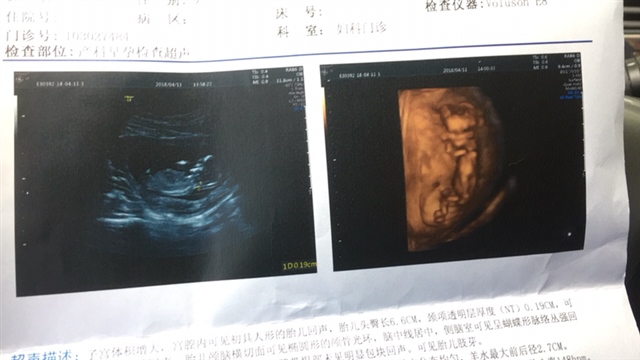

孕11周+0天

nt结果是当天出吗

[帖主]:当天出的